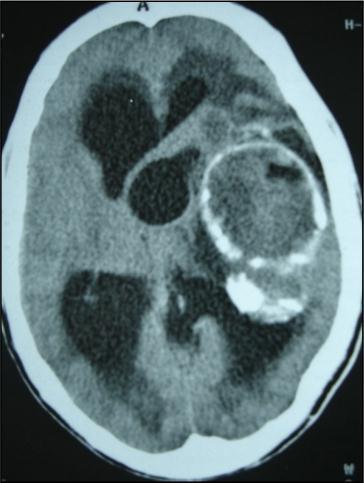

A 27 years-old male patient was admitted with 1 month history of headache, fever, short term memory lack, aphasia, right hemiparesis and seizures. He had liver hydatid cysts excised 8 years before and was treated with adjuvant medication (albendazole). The neurological examination revealed right central third cranial nerve palsy and hemi paresis, with Babinski sign positive, aphasia and papilledema on ocular fundus. The Glasgow Coma Scale was evaluated to 10/15 (E:3; V:1; M:6). A brain CT scan showed a large left temporoparietal intracerebral multiple and calcified hydatid cysts, important mass effect with midline shift about 7 mm following by an obstructive hydrocephalus (Figure 1). Other cysts were found in thalamic region (Figure 2). The Thoraco-abdominal CT scan showed multiple intra peritoneal hydatid cysts (Figure 3). A left temporo parietal craniotomy was performed in emergency. After corticectomy, using Arana-Iniguez technique, the appearance of the capsule suggested infected hydatid cysts with a purulent material which was aspirated. Numerous hydatid cysts were lifted away and several daughter vesicles were carefully removed without rupture (Figure 4). Macroscopically, the abscess wall appeared to be thick, calcified and tightly attached to lateral ventricular, so it could not be removed. The deep cyst overlying the third ventricle was left.in place. Microscopic examination demonstrated live scoleces, protoscoleces and multiple hooks. These findings are consistent with hydatid cyst (granulosis ecchinococcus) (Figure 5). Bacteriology examination found several white blood cells in the pus (neutrophilia) and infection by streptococcus pneumonia. This was consistent with infection. After surgery, the patient had medication (albendazole, specific antibiotherapy and phenobarbital). The inflammation assessment in the blood showed leukocytosis, a high C-reactive protein rate and increased erythrocyte sedimentation rate. Post operative CT scan was performed and showed the residual calcified capsule and decreased ventricular size (Figure 6). Clinical improvement was achieved after treatment. One month after the initial diagnosis, CT scan of the brain showed no recurrence and a physical examination revealed a neurologically intact, fully functional patient and eyes fundus normal. He was discharged and went to abdominal surgery two months later with complete intra abdominal cysts removal. Albendazole treatment was continuing for six months and radiological exploration was performed by brain MRI with spectroscopy at three and six month later. This showed that infection had resolved and the deep cyst overlying the third ventricle is less spherical (Figure 7, Figure 8). Four years later, the outcome was good.

Figure 2.axial CT showing another cyst located in thalamic region

Figure 6.post operative CT scan showing the residual capsule.